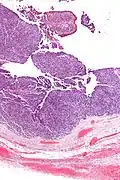

| Micrograph of transitional cell carcinoma of the ovary. H&E stain. |

Transitional cell carcinoma of the ovary (TCC of the ovary) is a rare type of ovarian cancer that has an appearance similar to urothelial carcinoma (also known as transitional cell carcinoma).[1]

TCC of the ovary is diagnosed by examination of the tissue by a pathologist. It has a characteristic appearance under the microscope and distinctive pattern of immunostaining.[2]

It is not related urothelial carcinoma.[1] It is in the transitional cell category of ovarian tumours which also includes malignant Brenner tumour and benign Brenner tumour.

Low mag. -